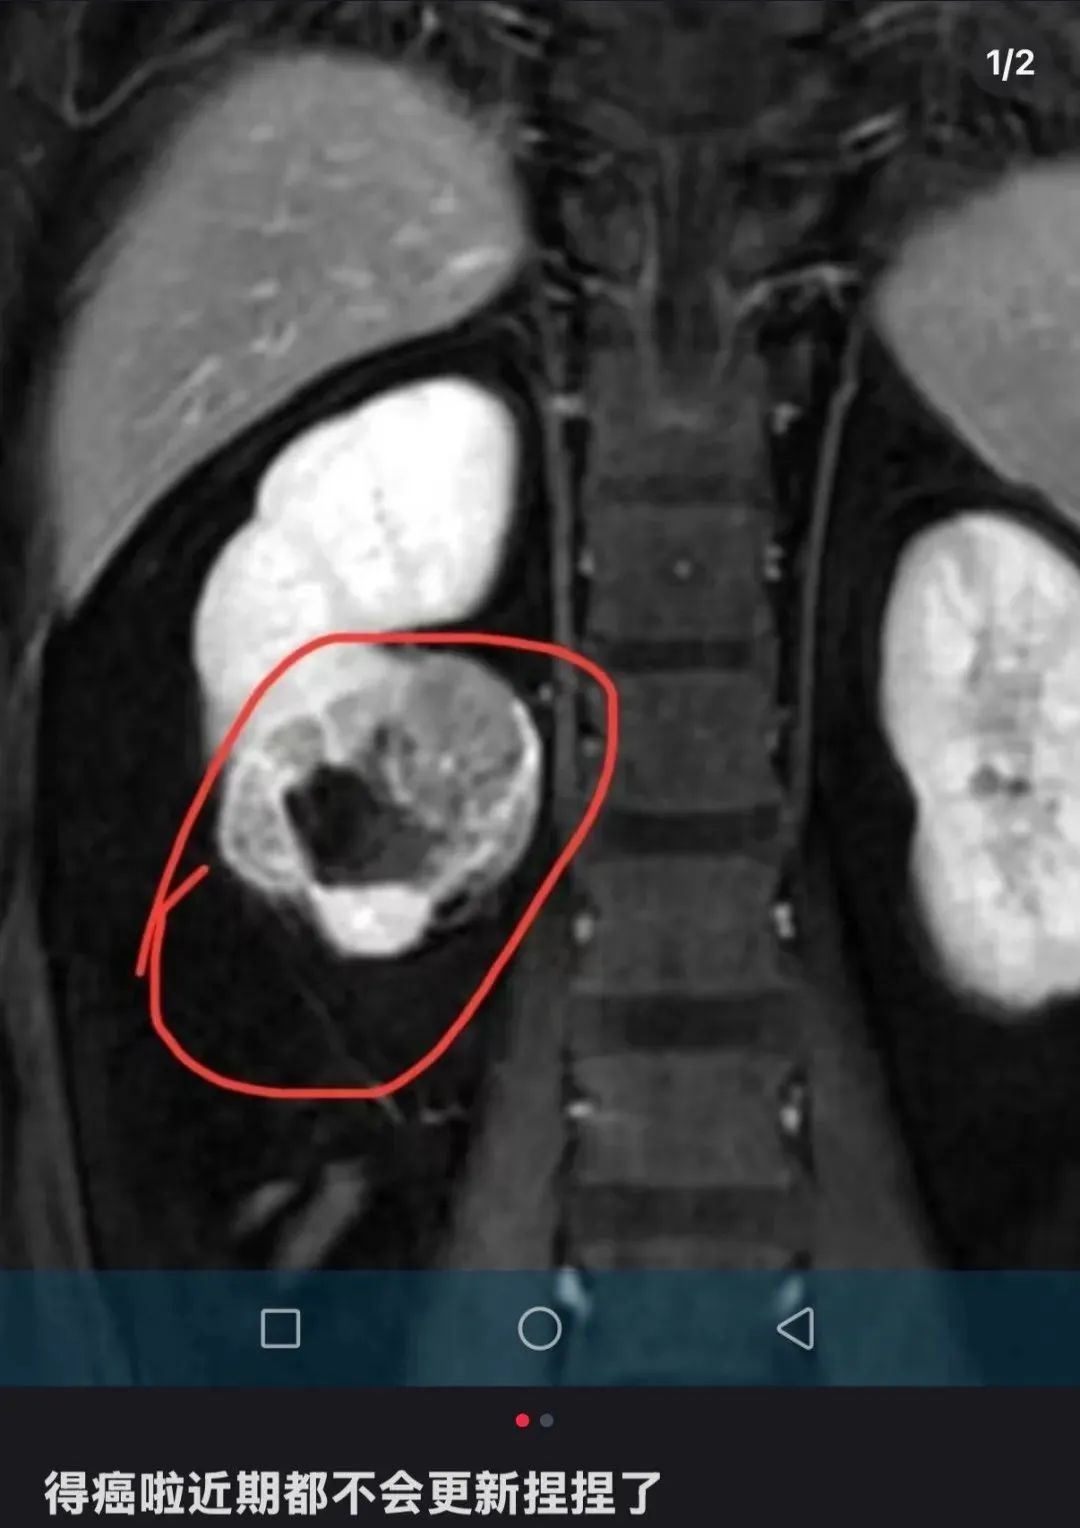

该博主在社交媒体上发文透露自己罹患肾癌,并宣布将暂时停止更新与“捏捏”玩具相关的视频内容。该博主最新更新透露病情:肾脏有部分坏死,即将进行手术。

△ 该博主在社交平台宣布罹患癌症。图源其账号截图